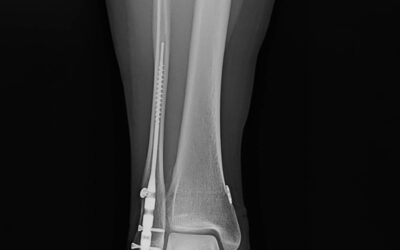

lerEXPO Highlights: Fibular Nails–Fad or New Standard?

This article synthesizes the key findings, surgical techniques, and clinical insights from a lerEXPO’s 2025 Gait Keepers Journal Club regarding the use of intramedullary fibular nails for distal fibula fractures. The primary focus is on a retrospective multi-center study published in the Journal of Foot & Ankle Surgery (JFAS) in 2023, which represents the largest cohort of its kind to date.

The transition from traditional Open Reduction Internal Fixation (ORIF) with plates and screws toward intramedullary fibular nailing represents a significant paradigm shift in ankle fracture management. While historically reserved for “train wreck” patients–those with compromised soft tissue, diabetes, or advanced age–current clinical evidence suggests that fibular nails are highly effective for simpler fracture patterns, such as stress-positive Weber B fractures.

By Brian Burgess, DPM with Brad Abicht, DPM, FACFAS and Jeff Dikis, DPM